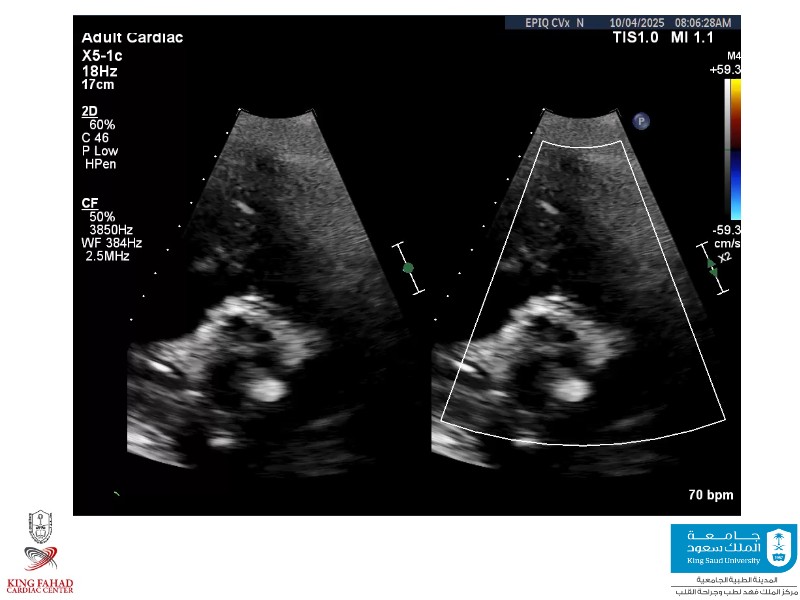

This session helps you anticipate and address complex scenarios such as mitral valve-in-valve, TAV-in-SAV, and valve-in-valve-in-valve procedures. Learn from expert case discussions that explore procedural strategies, technical challenges, and best practices to optimize outcomes in redo structural heart interventions.

- To anticipate and manage second valve scenarios with SAPIEN 3 Ultra RESILIA, including mitral valve-in-valve, TAV-in-SAV, and TAV-in-TAV

- To understand procedural strategies and challenges in complex redo scenarios using SAPIEN 3 Ultra RESILIA